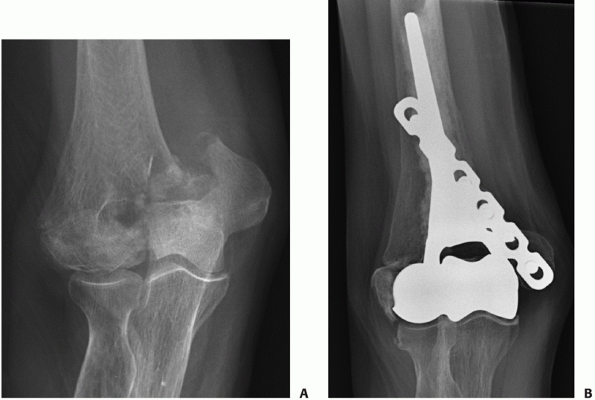

![]() |

FIGURE 33-18

A 73-year-old woman with a comminuted intra-articular fracture of the medial column (AO/OTA type B1.3) treated with ORIF via an olecranon osteotomy (A-C). |